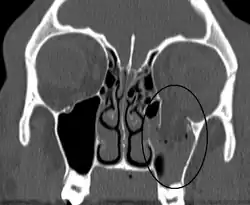

| An orbital blowout fracture of the floor of the left orbit. | |

Thin cut (2-3mm) CT scan with axial and coronal view is the optimal study of choice for orbital fractures.[16][17]